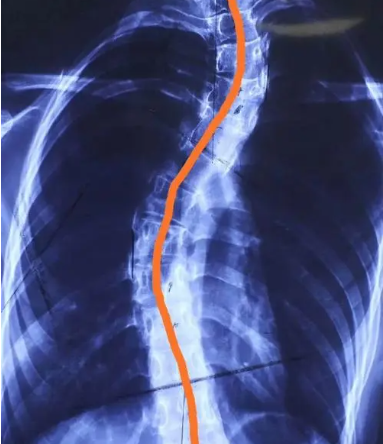

不规范的坐姿不仅仅会影响体态,身体也是越来越垮了!什么高低肩、盆骨前倾、脊柱侧弯都接踵而至.......

甚至有时候还会莫名其妙出现头晕眼花的情况,最后去医院检查竟然诊断出了严重的脊柱侧弯到压迫神经!

在坐下时正好和脊椎贴合,给到脊椎和盆骨支撑,侧翼也能为腰部提供支撑和保护,使脊椎呈现自然S型。

矫正坐姿,让脊椎变成漂亮的S型,不会让孩子脊椎变形,有助于孩子的发育!